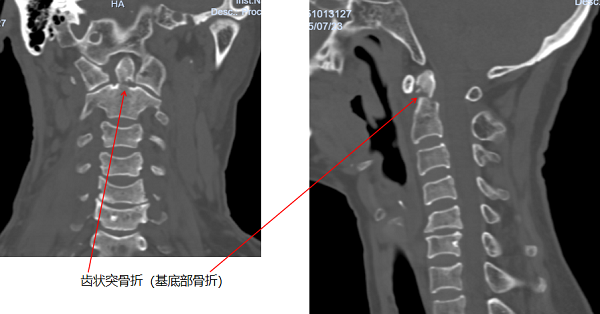

据悉,老奶奶在田间劳作时,不慎从2米高的田埂跌落至沟中,被救护车送至当地医院后,CT检查提示颈椎骨折,随即紧急转入玉溪市人民医院。进一步检查中发现,老人伤情复杂,不仅存在颈椎齿状突骨折、胸腰椎多发骨折、双侧腕关节骨折,还合并头部硬膜外血肿,病情危急。